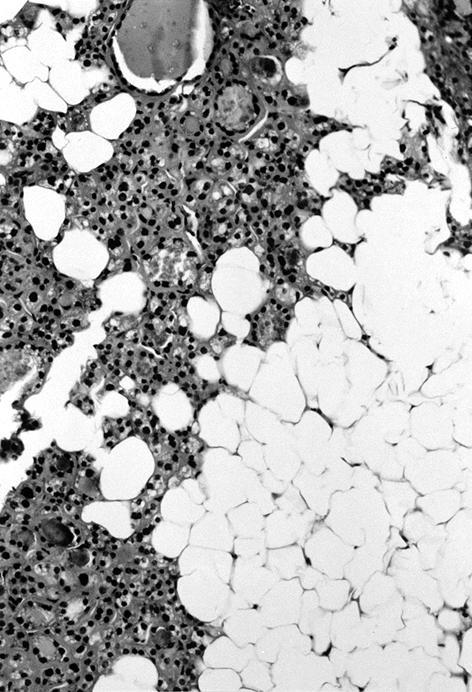

Microscopic (histologic) description

- Variable sized dilated follicles with flattened to hyperplastic epithelium

- Nodules may be present but without thick capsule

- Nodules with variable histological patterns: from colloid and microfollicular to hypercellular / microfollicular

- Secondary changes may be seen, including foci of fresh or old hemorrhage, rupture of follicles with granulomatous response, fibrosis, calcification and even osseous metaplasia

- Some of the cystically dilated follicles may show papillary projections (Sanderson polsters) that may mimic papillary carcinoma; however, they lack the nuclear features of papillary carcinoma

- Cytologic atypia (in the form of highly atypical nuclei) if exposed to radioactive substances

- Non nodular thyroid is reduced and compressed

- Incidental papillary thyroid microcarcinoma may coexist